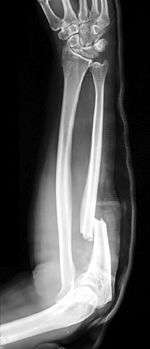

X-ray of Monteggia fracture of right forearm | |

The Monteggia fracture is a fracture of the proximal third of the ulna with dislocation of the head of the radius. It is named after Giovanni Battista Monteggia.[1][2]